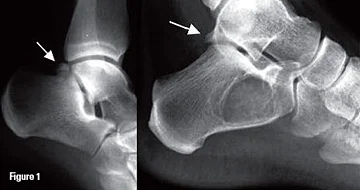

The two most common forms of bony impingement are a Stieda process, an enlarged posterolateral talar process, and an os trigonum, a secondary ossification site of the talus which does not fuse in teenage years remaining as an accessory bone, present in 7 – 14% of adults (Giannini, Buda et al. 2013). An enlarged calcaneal tuberosity can create the same issues (Hess 2011) but is less described in the literature.

A patient with a fracture of the Stieda process

Os trigonum (left), Stieda process (right)